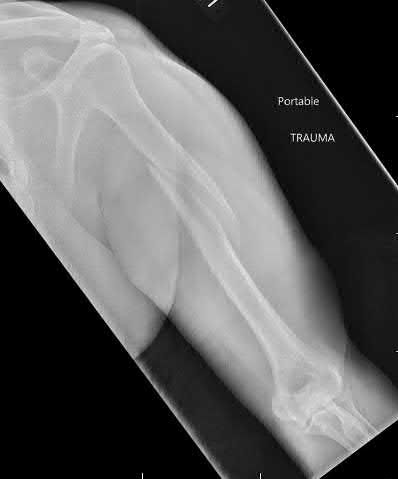

A 55-year-old patient presents with a slowly enlarging, painful mass in the proximal humerus.

Biopsy reveals a hyaline cartilage matrix with cellular atypia, confirming a diagnosis of central conventional chondrosarcoma. Which of the following genetic mutations is most frequently identified in this specific tumor?

Mutations in the isocitrate dehydrogenase genes, IDH1 and IDH2, are found in up to 50-60% of central conventional chondrosarcomas and enchondromas. EXT1 and EXT2 mutations are characteristic of multiple hereditary exostoses (osteochondromas). GNAS mutations are seen in fibrous dysplasia. TP53 and RB1 mutations are hallmark aberrations in osteosarcoma.